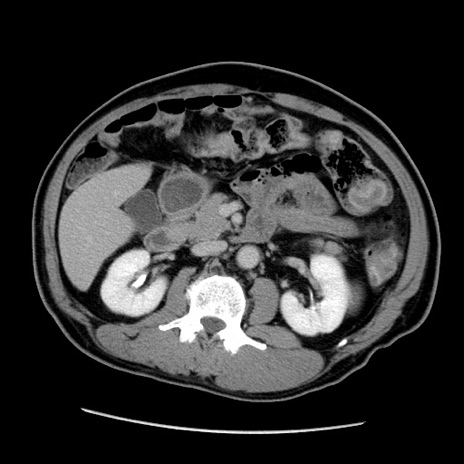

症例22(横断像)

【症例】50歳代男性

【主訴】腹痛

【現病歴】AVMからの被殻出血のため回復期リハ病棟入院中。 本日午後3時頃急に下腹部痛が出現した。

【既往歴】AVM、被殻出血、虫垂炎、高血圧

【身体所見】意識晴明、左半身不全麻痺、会話の理解は良好、36.5°C、腹部:膨隆、全体に板状硬、下腹部正中に圧痛点あり、反跳痛-、筋性防御不明、右下腹部にope scar

【データ】WBC 9400、CRP 0.06